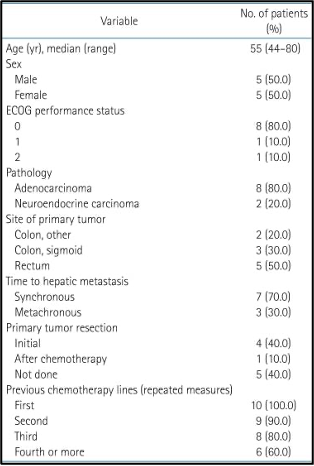

המאפיינים הדמוגרפיים והבסיסיים של 10 המטופלים שנרשמו לקבלת טיפול מוצגים בטבלה 1. הגיל החציוני היה 55 שנים (טווח של 44 עד 80 שנים). למטופל אחד היה סטטוס תפקודי של ECOG 2. קרצינומה נוירואנדוקרינית (Neuroendocrine carcinoma) נמצאה אצל 20%. לכל המטופלים שנרשמו הייתה היסטוריה של התקדמות לאחר לפחות משטר טיפול אחד של כימותרפיה.

להלן טבלה 1: מאפייני המטופלים

הטיפול הקודם

המספר החציוני של מחזורי כימותרפיה שניתנו לפני הרישום למחקר היה 23 (טווח של 1 עד 46).נעשה שימוש ביותר מ-10 מחזורים של כימותרפיה, למעט בשני מטופלים עם התקדמות נרחבת של גרורות בכבד לאחר התחלת משטר הכימותרפיה הראשון. מטופלים אלו לא יכלו לקבל כימותרפיה נוספת בשל החמרה בתפקודי הכבד. משטרי טיפול הכימותרפיה הנפוצים היו קפציטבין (capecitabine) ואוקסליפלטין (oxaliplatin) או פלואורואורציל (5-fluorouracil), עם לויקובורין (leucovorin) ואירינוטקאן (irinotecan) עבור אדנוקרצינומה (adenocarcinoma) או אטופוסיד (etoposide) עם ציספלטין (cisplatin) או אוקטריאוטיד (octreotide) עבור קרצינומה נוירואנדוקרינית (neuroendocrine carcinoma). משטרי כימותרפיה מפורטים מוצגים בטבלה משלימה 3. רדיותרפיה פליאטיבית (Palliative RT) ניתנה לשני מטופלים עם מסות ראשוניות (primary masses) ולמטופל אחד עם גרורות בעמוד השדרה (spine metastasis) עם דחיסה של חוט השדרה (spinal cord compression).

להלן טבלה משלימה 3: משטרי כימותרפיה מפורטים של המטופלים הרשומים